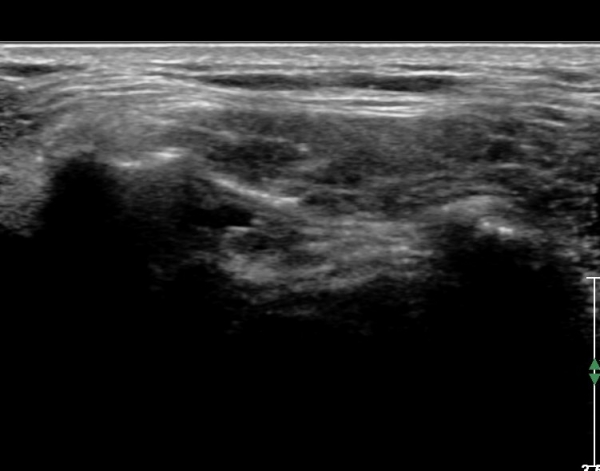

ÃÊÀ½ÆÄ ¼Ò°ß: ¿À±¸µ¹±â¿Í °ßºÀÀ» ¿¬°áÇÏ´Â ¿À±¸µ¹±â°ßº»Àδ밡 Á¤»óÀûÀÎ ¸ð½ÀÀ¸·Î °üÂûµÈ´Ù(»çÁø 1).

ŽÃËÀÚ¸¦ Á¶±Ý ¸»´ÜÀ¸·Î À̵¿ÇÏ´Ï ¿À±¸µ¹±â°ßºÀÀÎ´ë °ßºÀ ºÎÂøºÎ °ñ±ØÀÌ °üÂûµÇ°í Àδë

½ÉÃþºÎ¿¡ ¼ö¾×Àú·ù°¡ ÀÖ¾î ¸¸¼ºÀûÀÎ Ãæµ¹À» ÃßÁ¤ÇÒ ¼ö ÀÖ´Ù(»çÁø 2).